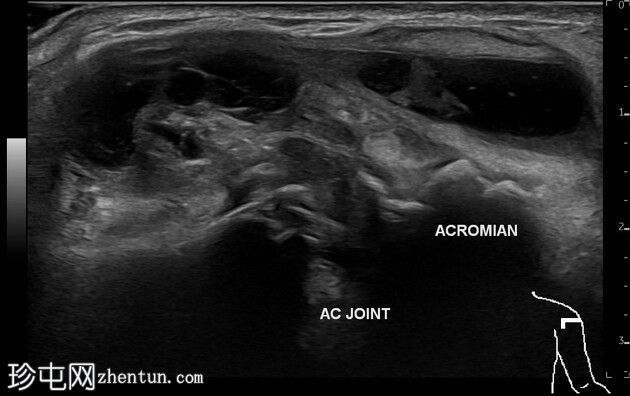

多平面

临床和X线片可见的肿块是一个起源于左侧肩锁关节并位于其上的不规则壁囊肿。囊肿内可见数个等回声至低回声区域,并伴有微小的强回声灶。囊肿周围及间隔可见血流信号。下方的肩锁关节可见关节囊增厚和骨质不规则。

该病例表现为典型的肩锁关节囊肿,其背景为较大的慢性肩袖撕裂。X线片本身也强烈支持该诊断。